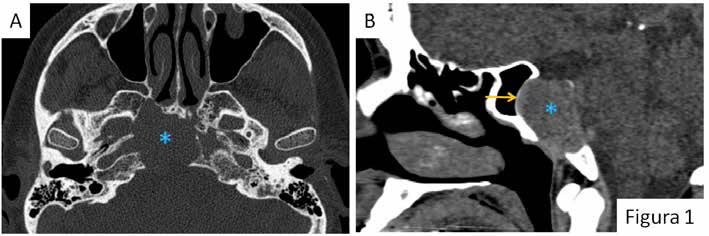

El paciente refería disminución del apetito sexual y disfunción eréctil de 10 años de evolución, con empeoramiento en los últimos 5 años, sin alteraciones visuales ni otra sintomatología asociada. Ante la sospecha de prolactinoma se inició tratamiento con cabergolina 0.5 mg hasta alcanzar la dosis de 1 mg dos veces por semana y se completó el estudio con pruebas de imagen (Figuras 1 y 2) confirmándose la presencia de un macroadenoma hipofisario ectópico. Tras cuatro meses de tratamiento, el paciente refirió clara mejoría de la clínica con normalización de los niveles de hormonas (prolactina basal: 15.5 ng/mL y testosterona total: 2.630 ng/mL).

La TC (tomografía computerizada) y la RM (resonancia magnética) pueden ser de utilidad en el diagnóstico preoperatorio, aunque supone un reto puesto que al ser una patología tan poco frecuente, es difícil incluir esta patología en el diagnóstico diferencial de rutina1.

Este tipo de lesiones se ven isointensas respecto a la sustancia gris cerebral en las secuencias T1 con captación heterogénea tras la administración de contraste.

Aunque no se evidencia un claro plano de separación con la hipófisis, la cual es de morfología y tamaño normales, existen diferencias en la intensidad de señal y debido al patrón de crecimiento en sentido caudal (en condiciones normales los macroadenomas tienden a crecer hacia la región supraselar que es donde existe menos resistencia), así como por su localización clival, a pesar del tamaño y de no tener la anatomía patológica se ha diagnosticado de macroprolactinoma clival ectópico.